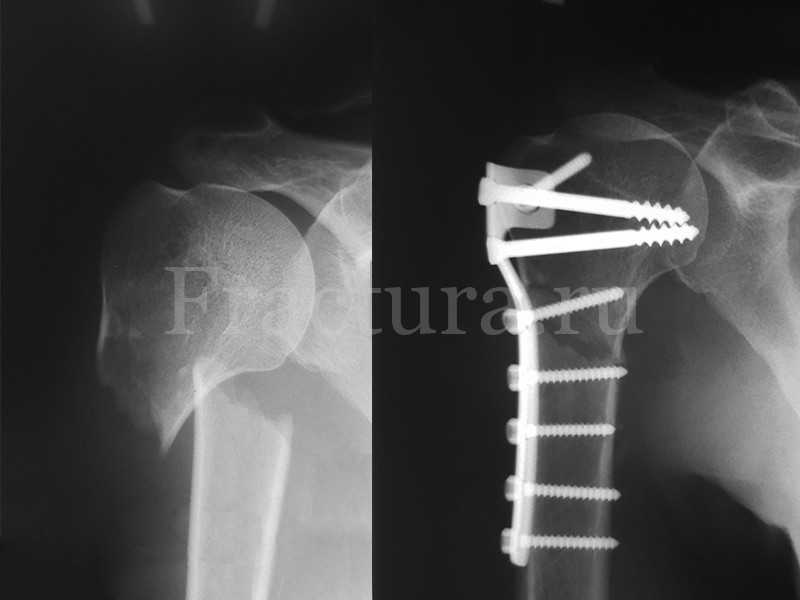

Медицинские снимки: Пластина в левом предплечье

Раздел: Альбом идей